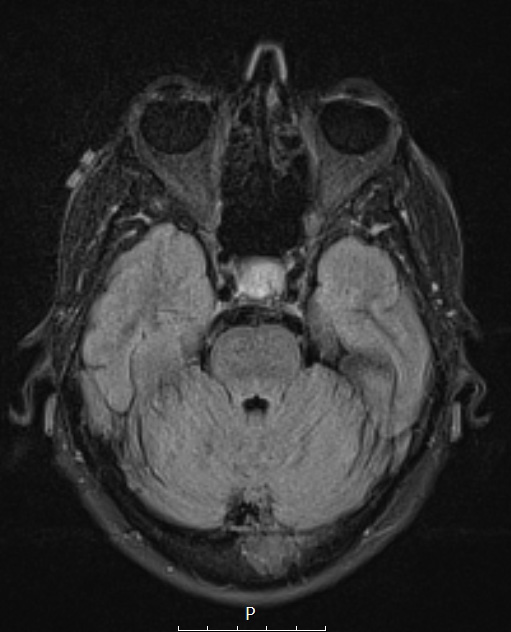

Case 4 History ---- The patient is a 57 year old woman with a sellar mass which has been treated conservatively for the last several years. Repeated MRI showed a slow increase in size. Radiological impression: Pituitary macroadenoma. Operative procedure: Transsphenoidal resection of pituitary tumor. ---- 4A1 MRI shows a T2/FLAIR hyperintense, homogeneously enhancing 1.2 x 1.3 x 1.3 cm mass centered within the left aspect of the sella with a signal that is indistinguishable from the pituitary gland. The mass displaces the pituitary infundibulum to the right and shows minimal extension into the left cavernous sinus.